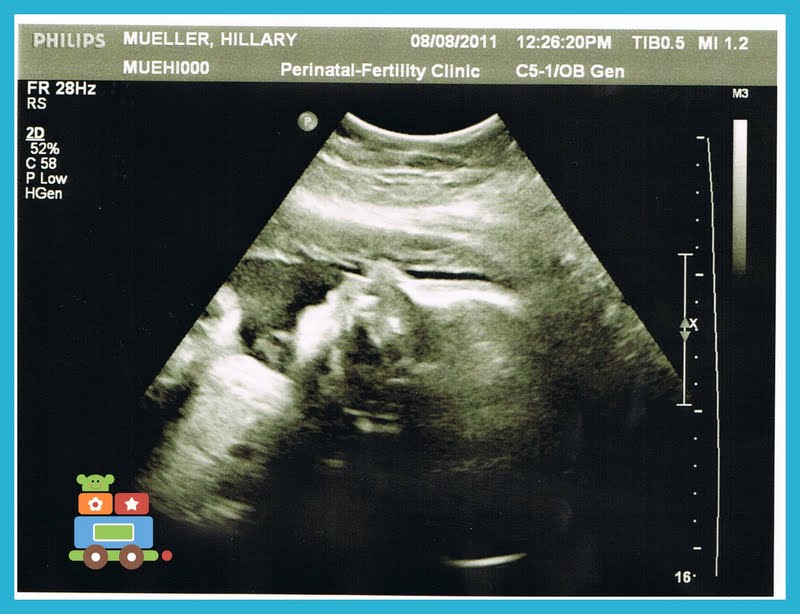

- Baby Boy now weighs 4 pounds 5 ounces!! (can I hear everyone say Praise God!)

- My cervical length was measuring in at 3.17 which is also awesome

- He is still measuring big and averaging 32 weeks and 6 days gestation (when I am only 31 weeks and 4 days)

- My AFI (amniotic fluid index) was only a 8.73 (which seemed low to me but the doctor assured me that it was more than fine)

And now for the best part... PICTURES! I'm pretty sure that even my hubby who reads my blog (bless his heart) during his lunch hour skips past all of the previous ramblings and skips right to the pictures! :)

I love seeing his face getting a little bit more chubby! And oh how I am going to kiss those sweet little lips of his every hour on the hour when he makes his big arrival!